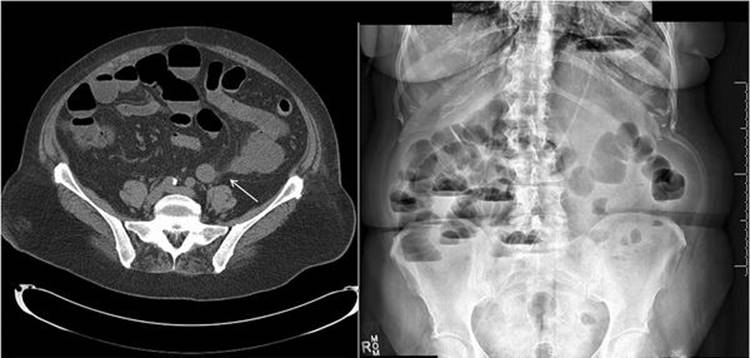

Fig. 6.5

Radiographic images of a patient with partial small bowel obstruction after abdominal sacral colpopexy. The CT scan shows distended loops of bowel with a transition point marked with an arrow